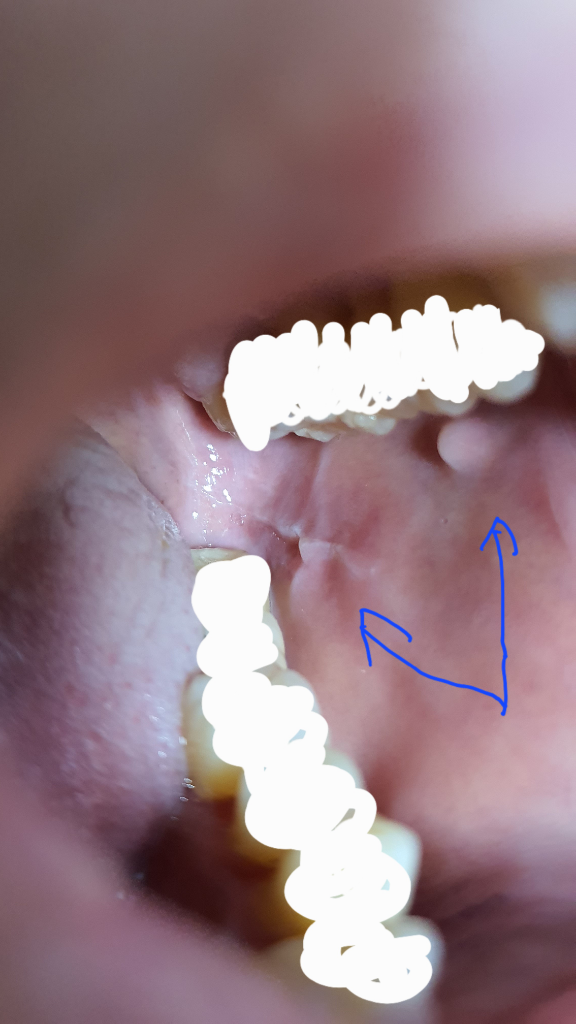

우연히 입 안을 봤는데 양쪽 다 무언가가 볼록 튀어나오고(물컹거림), 흰 줄이 마치 이빨 자국처럼 이빨이 닿는 부위에 나있는데 이게 뭔가요? 전혀 아프지는 않고 언제 생겼는지도 모르겠어요. 병원을 가야한다면 무슨병원을 가야할까요?

• 2번 째 사진

구강 백선이라는 질환입니다. 구강점막에 마찰이 지속되어 생기는 겁니다. 일종의 굳은살인것이지요. 특별한 치료는 필요없지만 이갈이 등이 있을때 생겨서 치과에서 확인해 보시는 것이 좋습니다.